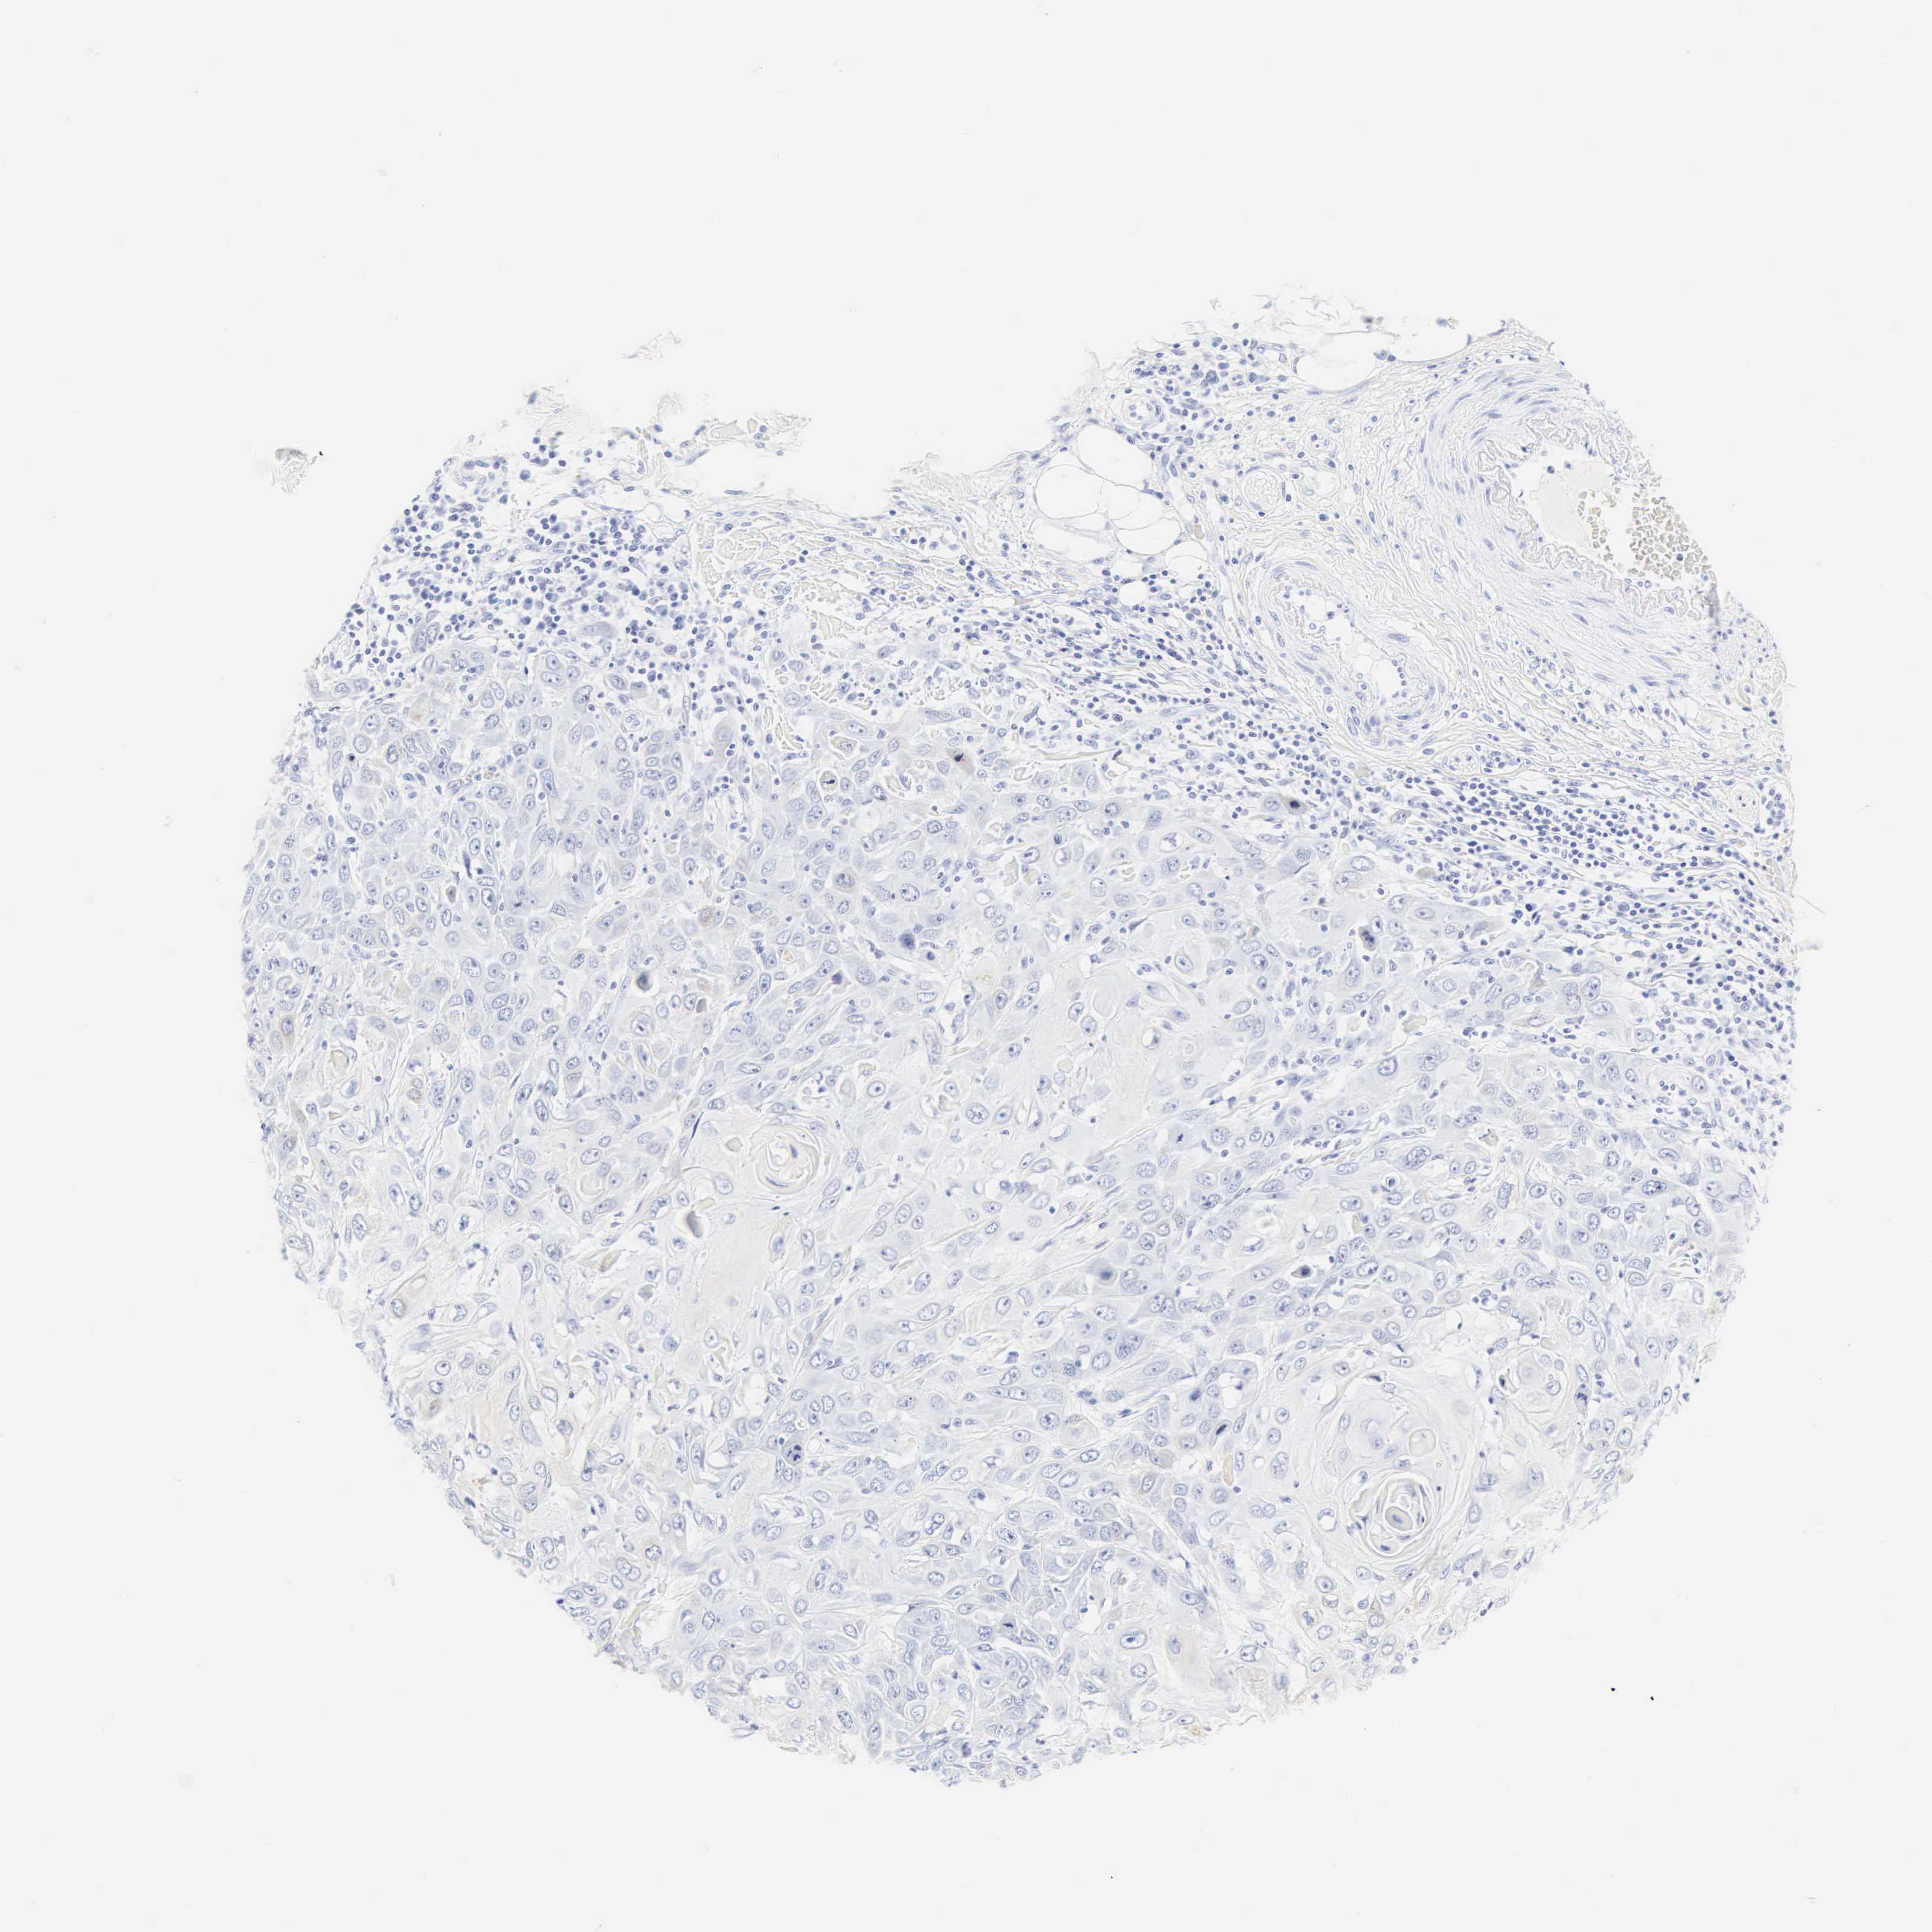

SKIN CANCER - Protein expressioni

A mouse-over function shows sample information and annotation data. Click on an image to view it in a full screen mode. Samples can be filtered based on level of antibody staining by selecting one or several of the following categories: high, medium, low and not detected. The assay and annotation is described here.

Antibody staining in the annotated cell types in the current human tissue is reported as not detected, low, medium, or high, based on conventional immunohistochemistry profiling in selected tissues. This score is based on the combination of the staining intensity and fraction of stained cells.

Each image is clickable and will lead to virtual microscopy that enables deeper exploration of all samples and also displays staining intensity scores, fraction scores and subcellular localization as well as patient and tissue information for each sample.

Antibody CAB000042

Basal cell carcinoma

Squamous cell carcinoma, NOS

Squamous cell carcinoma, metastatic, NOS